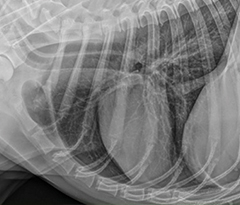

NEOVET est un générateur à rayons X créé spécifiquement pour les vétérinaires.

Avec une puissance de 32 kW, NEOVET permet de réaliser tout type de radiographie avec des APR adaptés (poids et épaisseur).